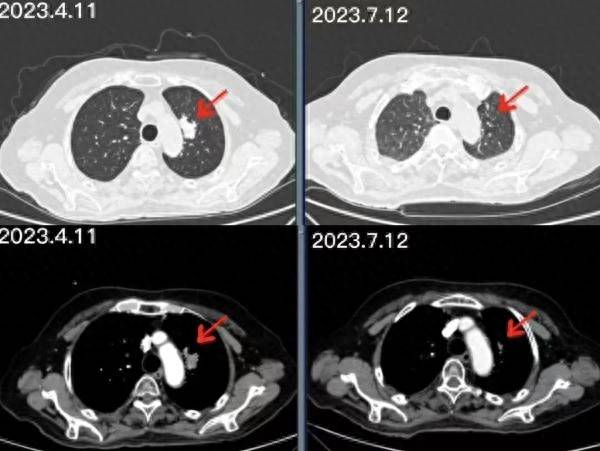

图 |张先生多次治疗后检查结果对比

进行了三个疗程的治疗后,复查发现,张先生肺部的肿块较前大幅缩小。“太感谢你们了!给了我重新活一次的机会!”